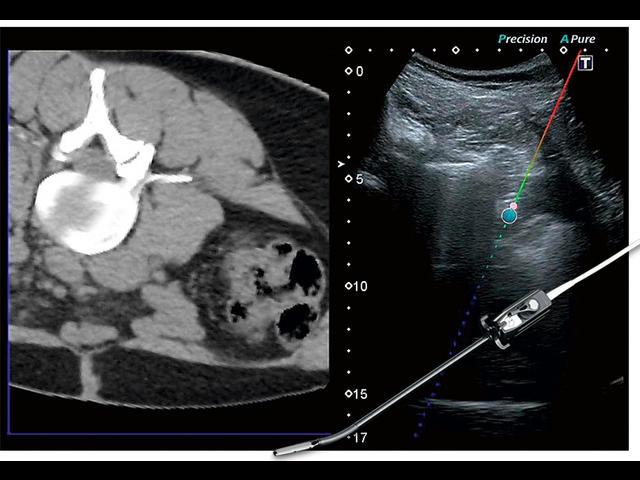

Обновленная версия легендарного УЗ-сканера. Стационарный аппарат экспертного класса Aplio 500 Toshiba NEW, визуализирует анатомические структуры в высоком разрешении. Модель позволяет выявить микрокальцификаты, новообразования, нарушения в работе сердца, сосудов и мышц. Присутствует функция виртуальной эндоскопии, 4D-сканирования, эластометрии тканей, УЗИ с контрастированием. За повышение качества изображения отвечают технологии ApliPure и Superb Microvascular Imaging. Первая задействует возможности пространственного и частотного кодирования, формирует цельный визуальный ряд с сохранением клинических маркеров. Вторая улучшает отображение микрососудистого русла, используя доплеровский эффект. Модель оснащена 21-дюймовым монитором, имеет 4 активных порта. Возможно подключение педиатрических, интраоперационных, лапароскопических и чреспищеводных датчиков.

IFusion: